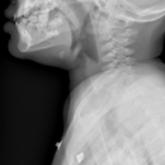

ArticleStridor in the Pediatric PatientAuthor:Garima Sarda, MDPublish date: October 4, 2018The distinct features of the pediatric airway make respiratory failure an important concern independent of the underlying cause.Read More